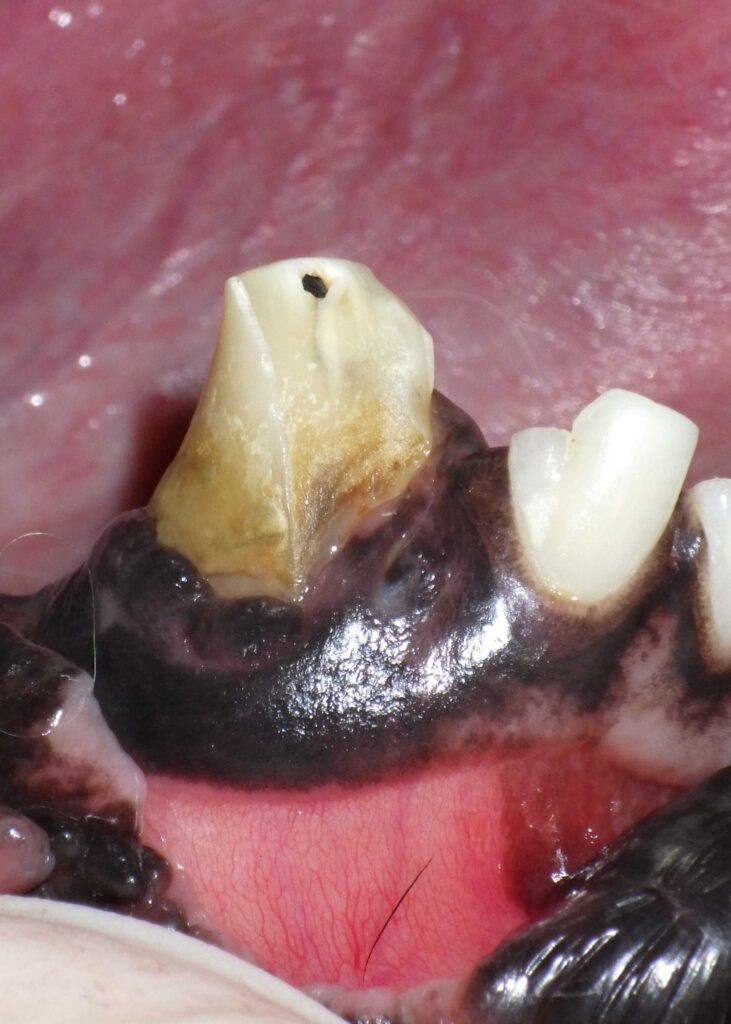

If your dog or cat chips, cracks, or fractures a tooth, itโs more than a cosmetic issueโitโs a painful medical

How Advanced Veterinary Dentistry Treats Broken Teeth in Pets Read Post ยป